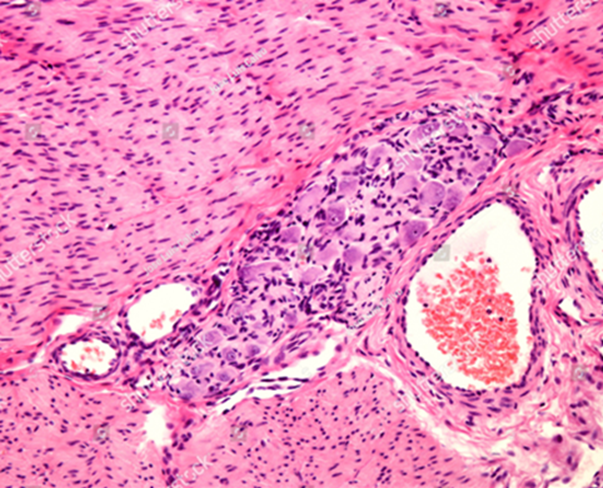

Препарат 1. Интрамуральный ганглий представлен скоплением нейронов, каждый из которых взаимодействует со вспомогательными клетками, которые рассматриваются в качестве аналогов шванновских клеток. Вблизи ганглия можно видеть профили кровеносных сосудов, которые залегают в прослойках рыхлой соединительной ткани в массиве мышечной оболочки стенки пищеварительной трубки (https://www.shutterstock.com/ru/image-photo/parasympathetic-terminal-intramural-ganglion-located-between-1829808125)